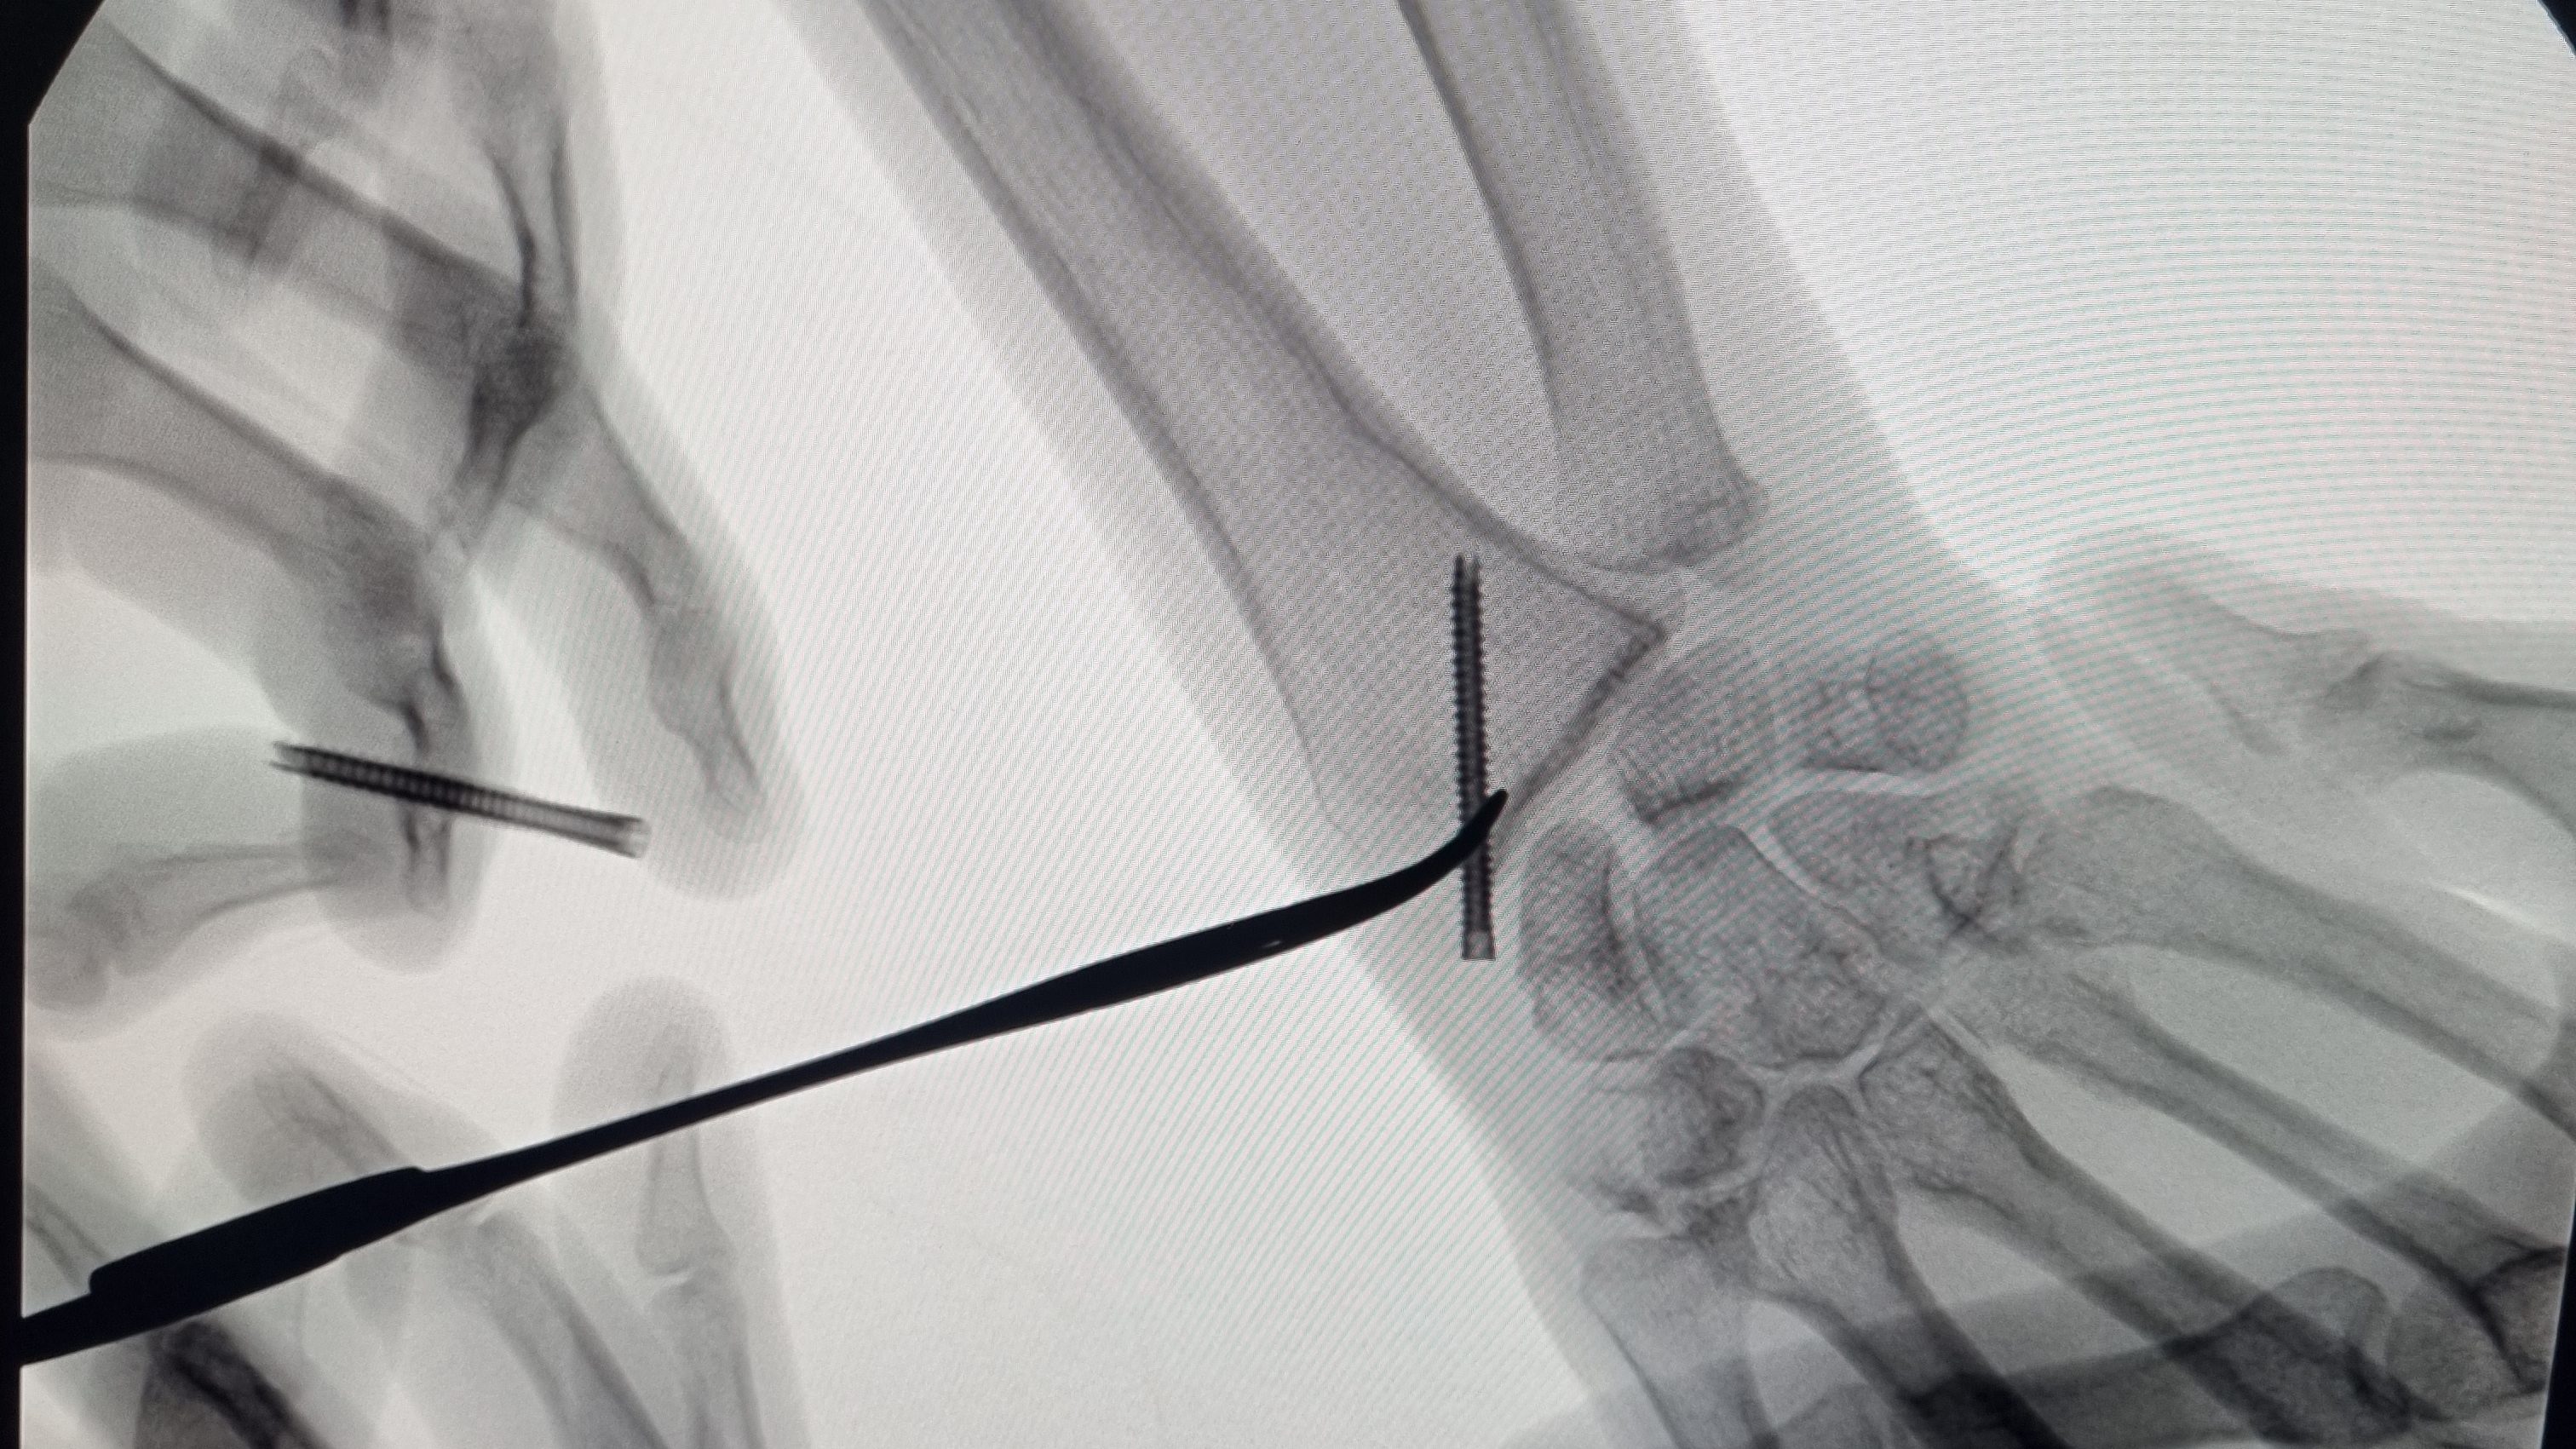

No caso de fraturas instáveis, ou com alta probabilidade de instabilidade, deve-se optar pelo tratamento cirúrgico, a fim de aumentar as chance de consolidação do osso em uma posição mais próxima do ideal possível. Para esse fim, utiliza-se materiais de síntese, as famosas placas e parafusos.

Exemplo de fratura da extremidade distal do rádio tratado com placa e parafusos